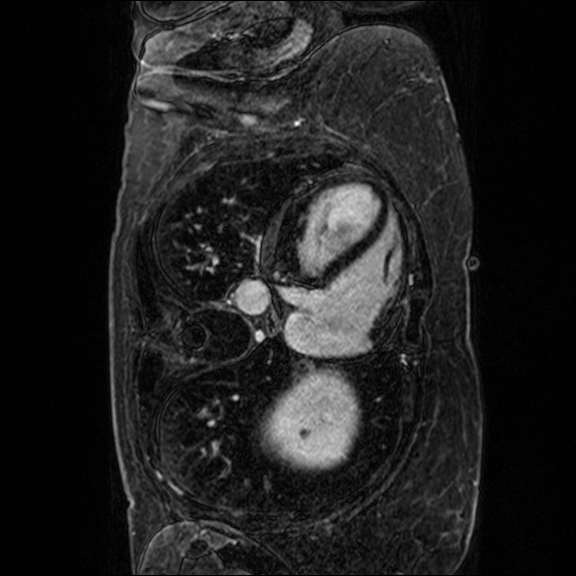

Late gadolinium enhancement magnetic resonance imaging (LGE-MRI) is typically used to provide quantitative information on atrial scars [25]. In this measurement, location and size in the left atrium (LA) indicate pathology (i.e., LA scars) and progression of atrial fibrillation [12].

Nowadays, deep learning models have been widely used to segment LA cavities and quantify LA scars from LGE-MRIs [3] to help radiologists with initial screening for quick pathology detection. Meanwhile, LGE-MRIs are often collected by multiple scanners and possibly in low imaging quality. Each of them produces inconsistent domain information [14], including different contrast and spatial resolutions. (1) Promoting the generalization of a segmentation model against domain inconsistency becomes another challenge.

The LAScarQS dataset includes two tasks: 1). LA and LA Scar segmentation (task 1), and 2). LA Segmentation across scanners (task 2). The first task contains 60 3D LGE-MRIs with labels containing LAs and LA scars, while the second consists of 130 3D LGE-MRIs from multiple medical centers with labels containing only LAs [12].